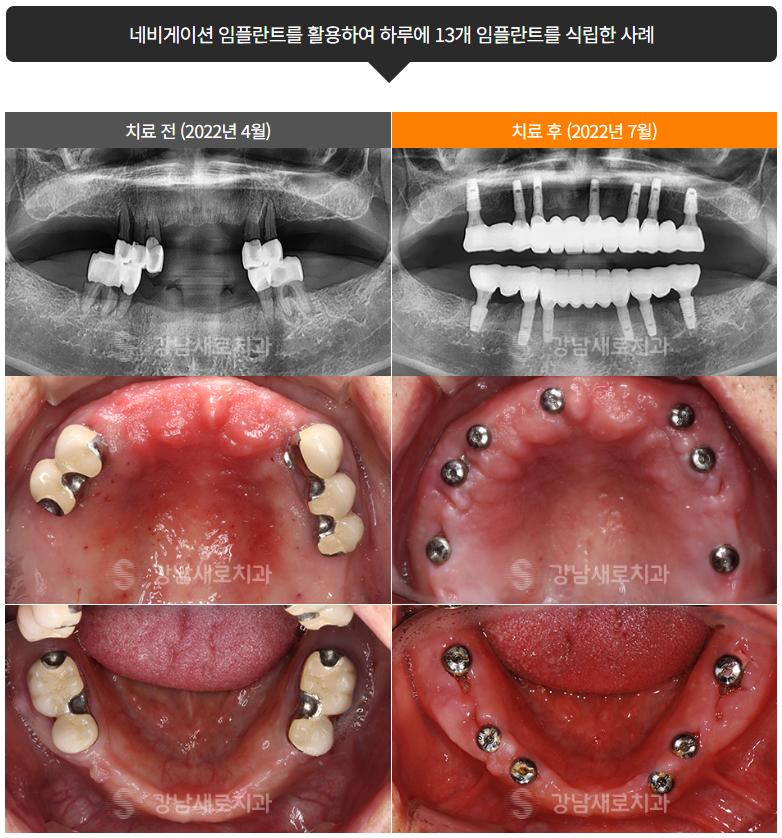

네비게이션임플란트

붓기, 출혈, 통증 최소화 임플란트

시간 단축 : 일반 임플란트는 절개와 봉합 과정 등 수술 시간이 다소 길지만 네비게이션 임플란트는 가이드 덕분에 무절개로 이루어져 붓기, 출혈, 통증이 적고 식립 시간을 단축시킵니다.

가이드를 기반으로 잇몸 절개 없는 임플란트 식립하여 붓기, 출혈, 통증을 줄이고 회복 기간도 보다 빨라지게 됩니다.